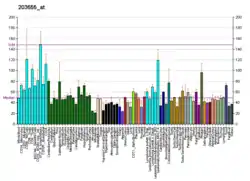

XRCC1 is over-expressed in non-small-cell lung carcinoma (NSCLC),[8] and at an even higher level in metastatic lymph nodes of NSCLC.[9]